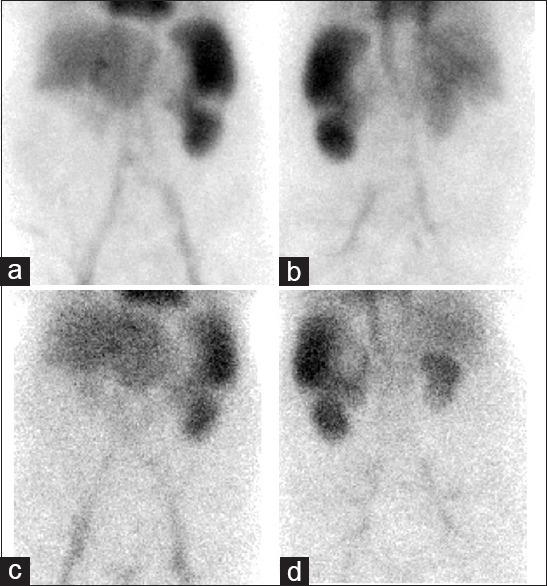

Patient with a history of overt gastrointestinal bleeding, diabetes mellitus, hypertension, polycythemia vera, and choledocojejunostomy was hospitalized because of hematemesis and melena. An area of Technetium-99m labeled red blood cells accumulation at the splenic flexure similar to an overt bleeding area, was observed on gastrointestinal bleeding scintigraphy (GIBS). In case of underlying malignancy, abdominal computed tomography was performed and demonstrated the infarction area placed laterally in spleen, appearing as a cold region on sctintigraphic image, separating the inferomedial and upper part of splenic uptake. Splenic variants and pathologies can complicate interpretation of GIBS.